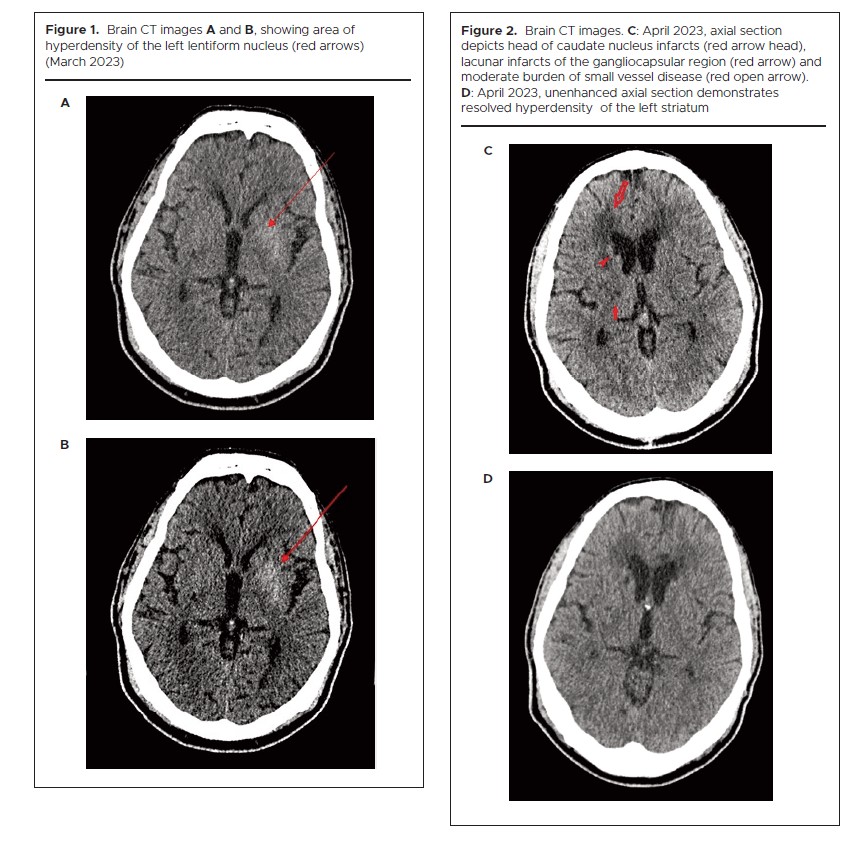

A CT scan completed on the same day ruled out an acute stroke. However, it showed an old lacunar infarct/gliosis of the right cerebellum, the head of the right caudate nucleus, the deep white matter and the gangliocapsular region; and background moderate small vessel disease. There was unilateral hyperdensity of the left lentiform nucleus, more prominent this time compared with previous images (Figure 1). The differentials considered for these hyperdense areas were mineralization or striatal lesions resulting from poorly controlled diabetes.

An MRI brain scan could not be completed due to patient agitation while in the scanner. A head CT scan was completed with no acute intracranial finding, i.e. intracranial haemorrhage, acute infarct or mass lesions. It did, however, show head of caudate nucleus infarcts, lacunar infarcts of the gangliocapsular region and moderate burden of small vessel disease (Figure 2).

1307 Figures 1 and 2

While ischaemic and haemorrhagic strokes can cause chorea,15,16 prior CT imaging obtained during the evaluation of our patient’s strokes did not demonstrate the prominent area of hyperdensity in the left lentiform nucleus that was reported on the current admission. The repeat CT scan findings on his last visit were unchanged from the initial hospitalisation. Chorea can sometimes persist or manifest later in patients with diabetic striatopathy,17 often reversing with normalization of glucose levels. It is possible that the chorea was triggered by the correction of the hyperglycaemia, much akin to the worsening of diabetic retinopathy with intensive glycaemic control.

We have presented a distinctive case of diabetic striatopathy in which chorea in association with a left lentiform nucleus hyperdense area on CT imaging initially resolved with correction of the acute hyperglycaemia. It subsequently worsened during the period of euglycaemia but responded well to anti-chorea medications. The rapid changes in the glucose milieu may have unmasked a quiescent striatal lesion from the longstanding poor glycaemic control. Complete resolution had not occurred at the time of discharge, indicating that symptoms may sometimes linger.